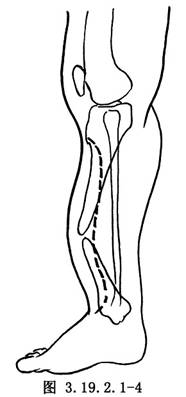

脛骨前內側做一弧形切口,從脛骨結節遠端開始,沿脛骨內後緣止於脛骨遠側的前方(圖3.19.2.1-4)。